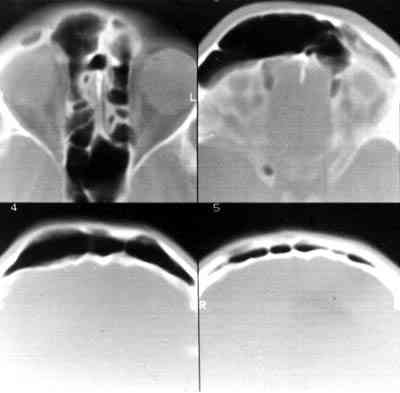

Figura 3

4 CORTES DE TAC EN PROYECCIÓN AXIAL MOSTRANDO EL SENO FRONTAL DERECHO HIPERNEUMATIZADO A DIFERENTES NIVELES. HACE 8 AÑOS Y PREVIOS A LA INTERVENCIÓN.